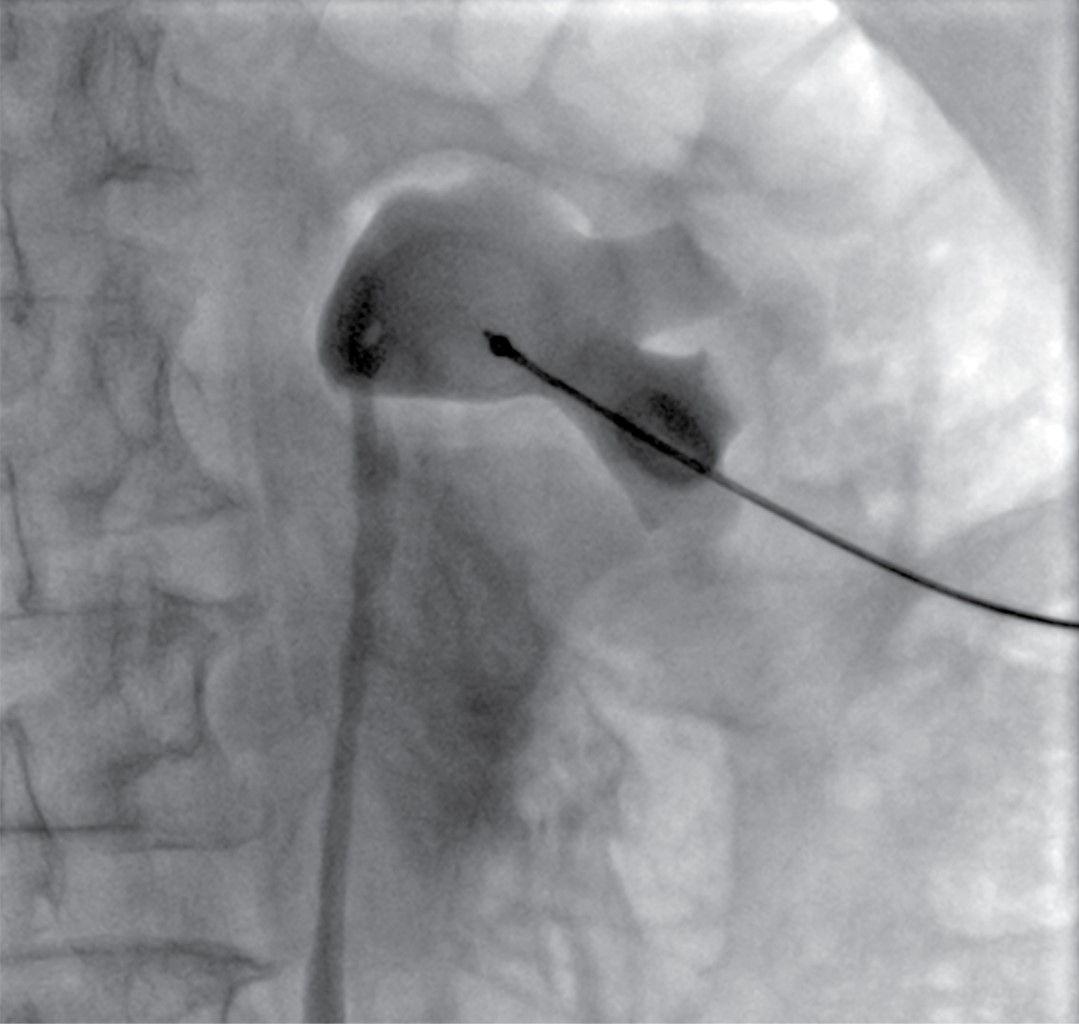

Percutaneous nephrostomies: 10-year experience at Angeles Mocel Hospital

Introduction: Percutaneous nephrostomy placement is increasingly common, with multiple imaging techniques for placement. The Brödel area is the most used for its placement. There are multiple indications for performing a percutaneous nephrostomy that includes benign, malignant causes, or surgical complications. Objective: To publicize the main causes of percutaneous nephrostomies at Hospital Angeles Mocel. Material and methods: A descriptive, retrospective, and observational study were carried out in which we present the experience in percutaneous nephrostomies at Hospital Angeles Mocel for 10 years, from the period January 2010 to December 2020. Results: A predominance was observed in the male gender with 59.10% in the cases, as well as the most frequent age group was between the 5th and 6th decade of life. Retroperitoneal hematoma was the most frequent cause of benign obstructive uropathy in 42.86% and prostate Ca was the most frequent cause of malignant obstructive uropathy in 23.98%. The complications presented were 1.35%, being the renal hematoma the most frequent. Conclusions: The placement of percutaneous nephrostomy is essential to resolve acute or chronic conditions. Found few differences between the literature and the study.

Figure 1

Figure 2

Figure 3

Figure 4

Figure 5